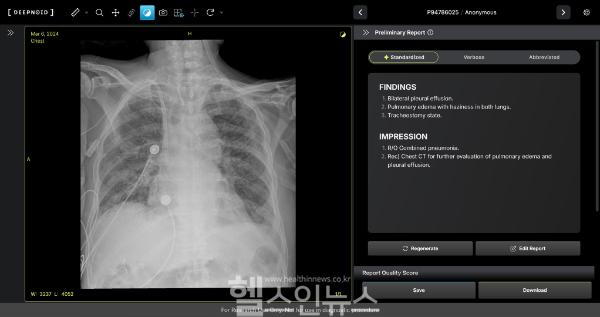

M4CXR은 흉부 X-ray 영상에서 41종 병변을 수초 만에 판독해 일관되고 신뢰성 높은 소견서 초안을 제공한다. 1000만 건 이상의 판독 데이터를 학습해 응급상황에서도 신속한 예비 판독 결과를 전달, 영상의학과 전문의를 보조해 진단 정확성과 속도를 높인다.